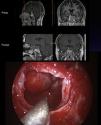

MethodsFrom February 2011 to August 2016, we conducted a prospective study on a series of 86 patients with pituitary adenoma, all of whom underwent surgery with a purely endoscopic endonasal approach. The ‘four hands-two nostrils’ technique was performed in all cases by a surgical team composed of an ENT surgeon and a neurosurgeon. Mean follow-up was 32 months. All patients were evaluated according to clinical, radiological and endocrinological criteria.

ResultsIn our series, 53% were women and 47% men. The age ranged from 14 to 84 years of age, with a mean of 54 years of age. The most common initial symptom was visual deficit (42%), followed by hormonal hyperfunction (21%), with acromegaly being the most common clinical syndrome. The most common tumours were non-functioning tumours (73%), while GH-secreting tumours (65%) were the most common functioning adenoma. Regarding tumour size, 76% were macroadenomas, 11% microadenomas and 13% giant adenomas. Approximately 63% of the adenomas exhibited suprasellar extension and 37% involved invasion of the cavernous sinus (Knosp grade ≥3). Total excision was achieved in 77% of the cases. After the intervention, visual improvement was achieved in 91% and remission of endocrine hyperfunction in up to a 73% of cases. The most common complication was anterior pituitary insufficiency of at least one axis (9%). There were no cases of postoperative cerebrospinal fluid fistula.